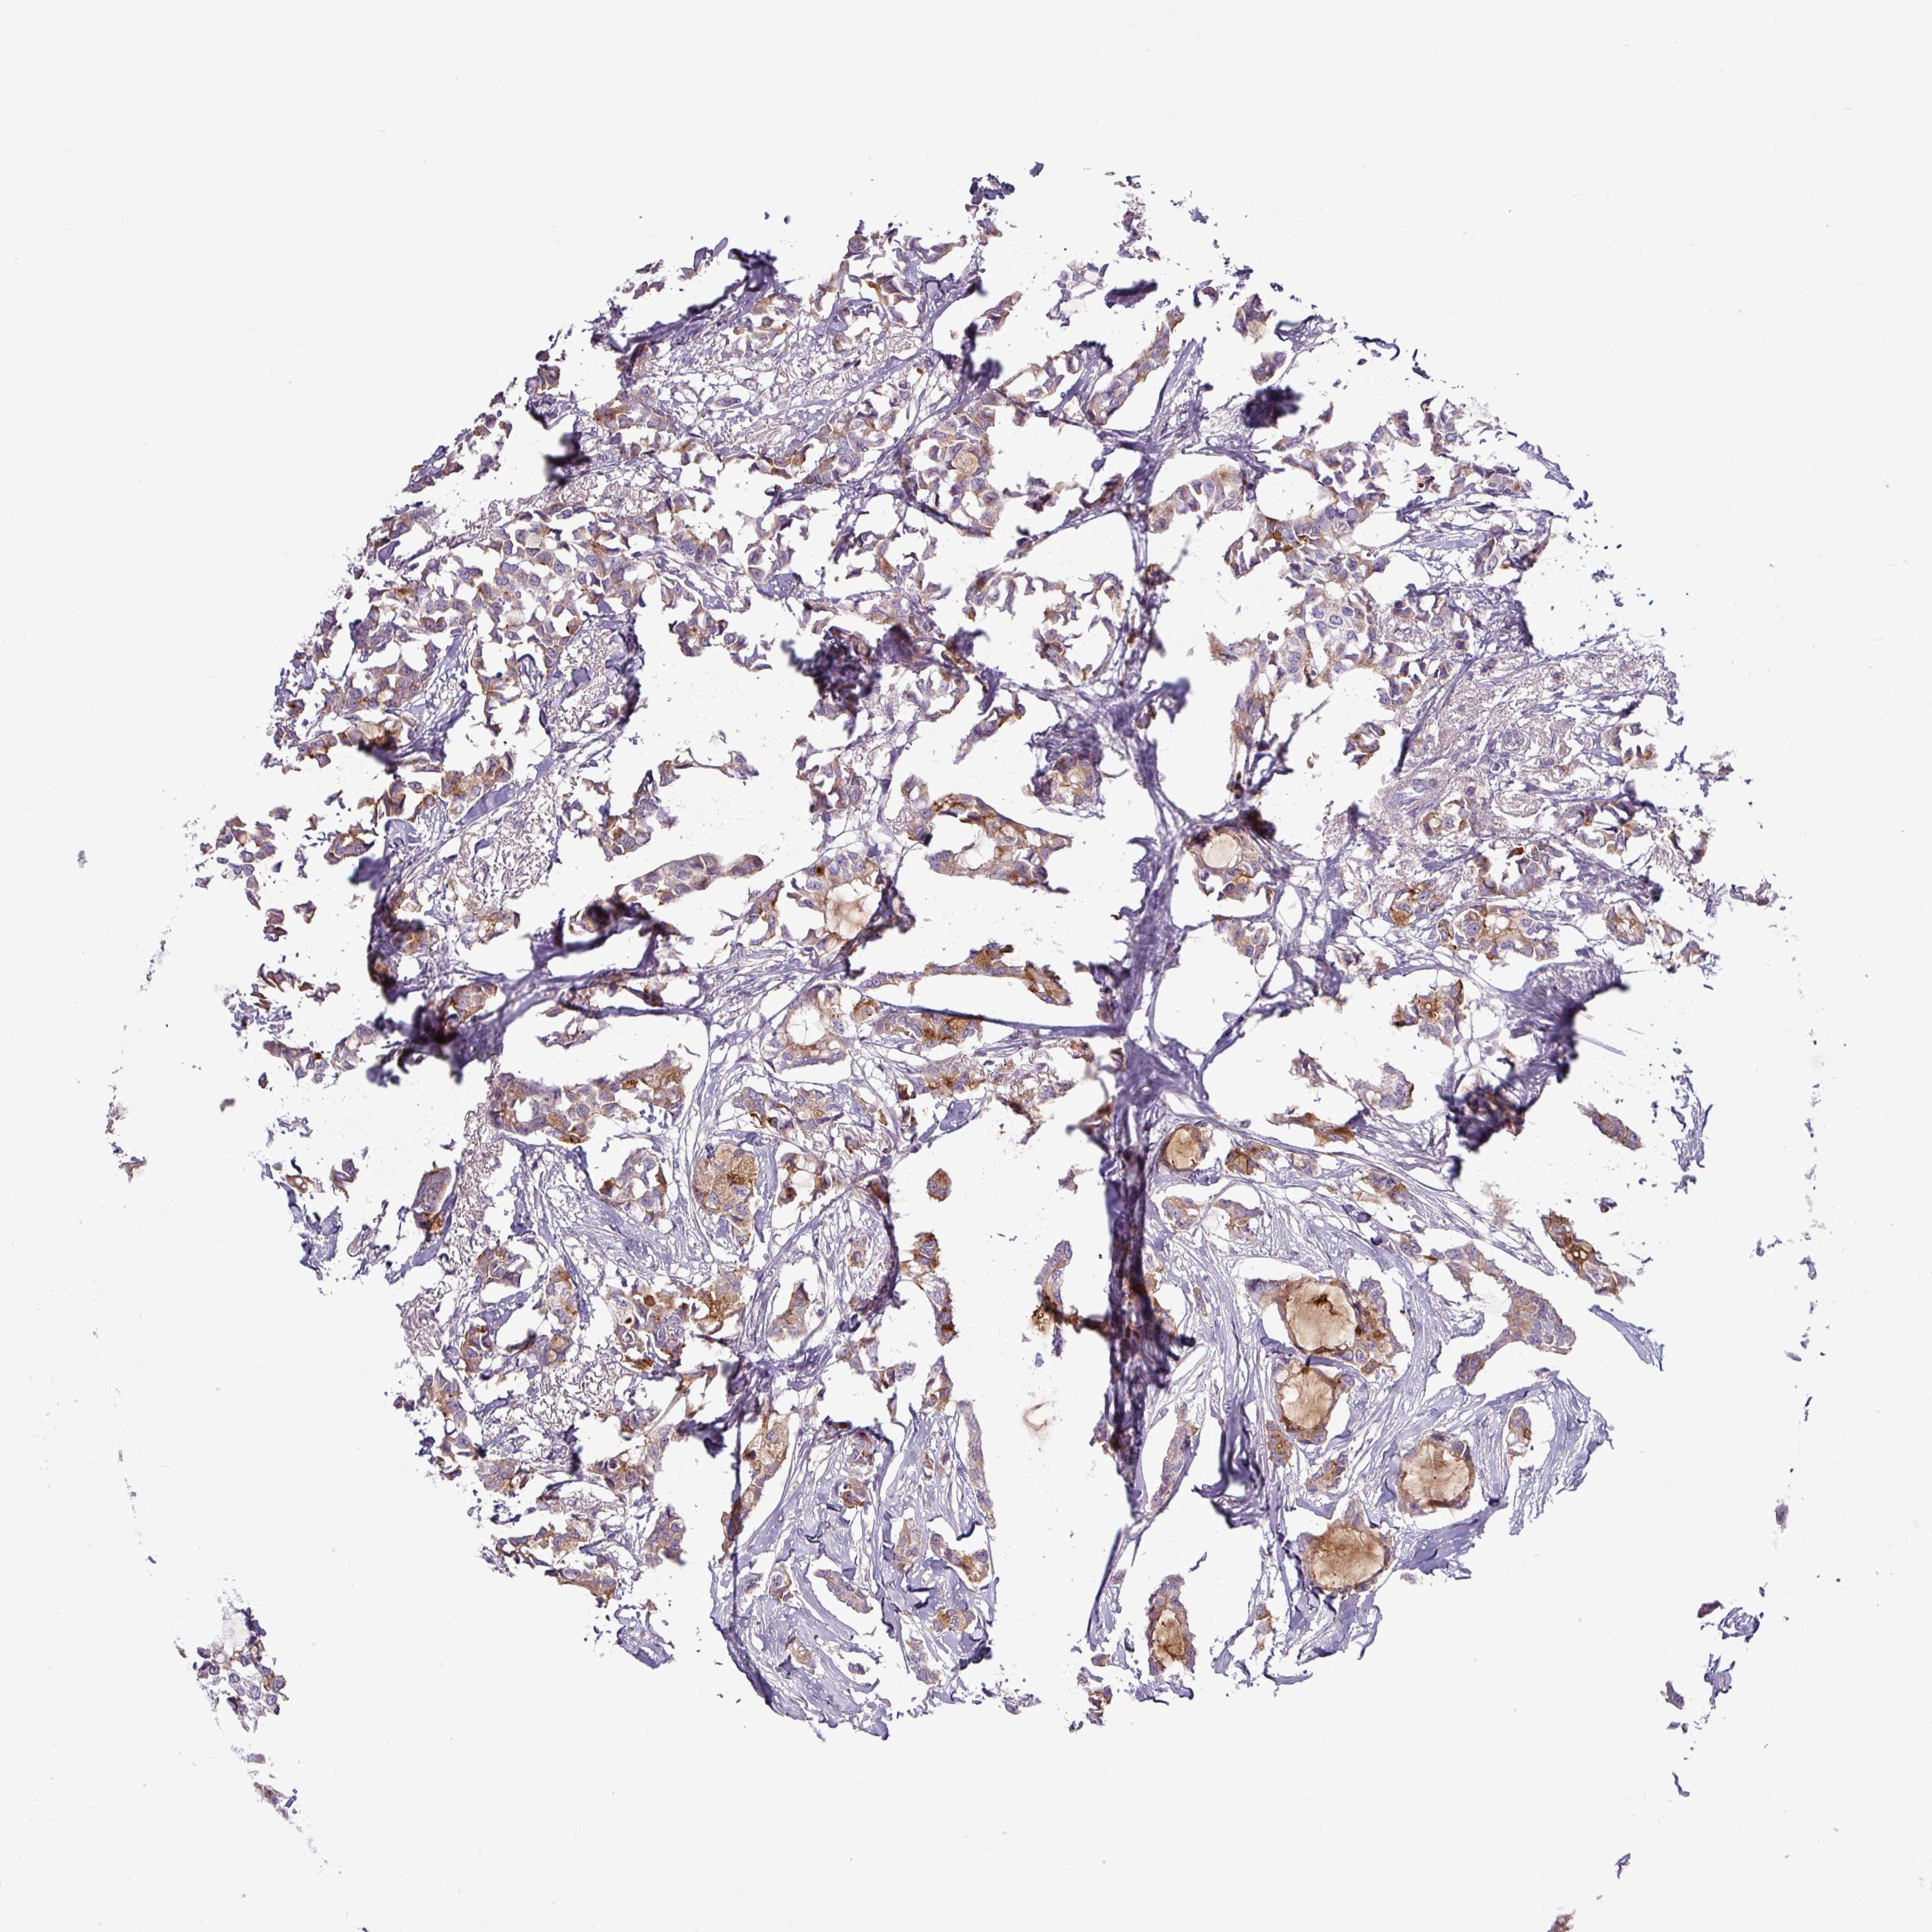

CANCER BREAST CANCER Show tissue menu

BRCA TCGA BRCA VALIDATION PROTEIN EXPRESSION